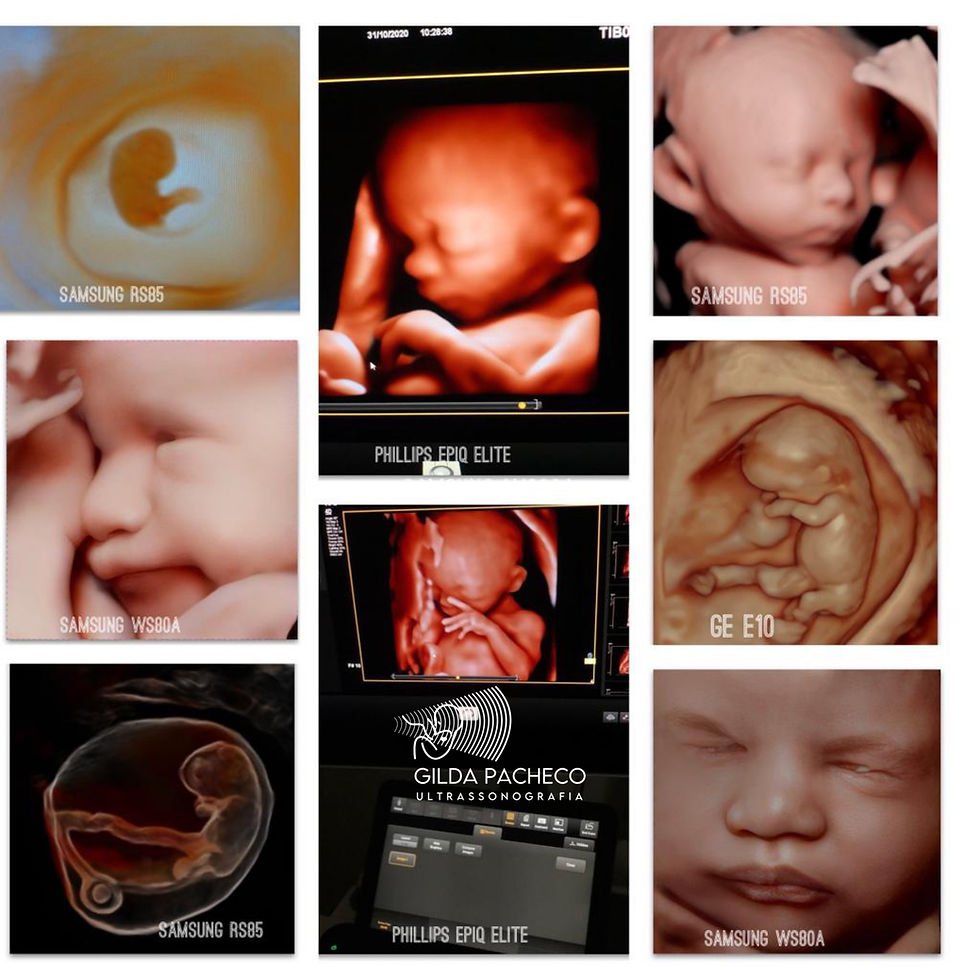

Havia ficado impressionada quando em uma aula de ultrassom o professor mostrou na tela uma imagem dizendo que aquela era a primeira imagem da vida. Inclinei o máximo que pude para buscar o melhor ângulo na sala de demonstração e enxergar o que ele mostrava. Estava eu ali, prestes a ver uma outra imagem que me fascinaria, outra retratação da Criação?Eu sempre fui aficcionada em imagem, em materialização de uma ideia e fiquei ali parada analisando: era a imagem da vesícula vitelina e do pequeno botão embrionário, de uma gestação em torno da quinta semana. Uma imagem muito simples, mas que conseguia tocar a minha alma. Olhando melhor, aquela imagem parecia muito um anel solitário, onde o embrião representava a pedra solitária. Minha mãe chama a pedra da jóia de “gema rara”. Fiquei emocionada ante a grandeza e o significado daquela imagem aparentemente tão simples. Compartilho com vocês essas imagens, porque hoje ao ler aquela notícia associei novamente as duas imagens da Criação e tinha que revelar o que descobri: coincidências da vida e da criação. Quando a gente enxerga com os olhos do amor, vê cores e coisas inimagináveis e descobre o amor oculto em todas as obras do Criador.

Qualquer um que faça ultrassom na quinta semana de gravidez vê essa imagem do anel. Eu nunca perco a oportunidade de enfatizar para a mãe que essa é a primeira imagem da vida, que a “gema rara” desse anel solitário é o embrião. Que essa jóia de incalculável valor está parcialmente lapidada e que está sendo entregue a ela como um presente do Criador, para que ela zele, cuide e receba com alegria. A analogia é perfeita! Difícil encontrar uma mãe ou um pai que não chore. Eu sempre fico com os olhos marejados, choro também as vezes. A minha revelação é que, com meu trabalho sinto-me quase tão importante quanto Michelângelo com o seu pincel, retratando o momento da Criação. Ele levou 4 anos para pintar; eu não apenas retrato, mas também vejo em tempo real, quase todos os dias, as pulsações cardíacas dos primeiros momentos de vida da criatura humana e não levo mais que 10 minutos para isso. Nesses instantes sinto que Deus habita em mim! Como mostra o afresco de Michelângelo: tão perto de mim, que até posso tocá-lo!